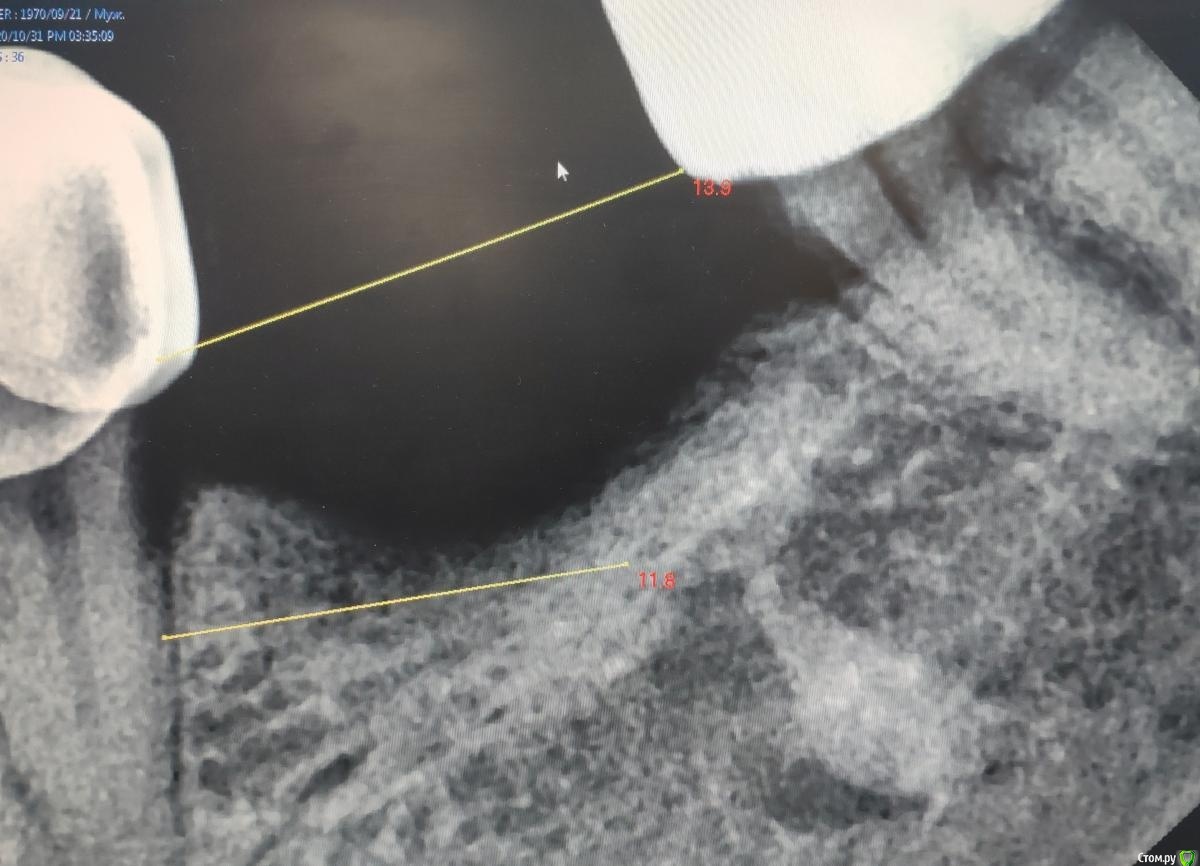

Женька Опубликовано 3 ноября, 2020 Автор Поделиться Опубликовано 3 ноября, 2020 Не скажу что у меня много с этим опыта. Но если мешает для установки импланта, то удалять. Если пациент долго ходит (у меня такой сейчас уже 20 лет с примерно так же похороненным корнем) и имплантация не планируется я бы предупредил пациента и ненастойчиво предложил удалить)) Сделайте скрин среза с размерами до корня, просто непонятно как он глубоко сидит и что вокруг него.Вот такие... но тут как то и не похоже на апекс?Имплантации мешает, но даже если пройтись сверлами и надеяться на полное разрушение этого дела, останутся поднутрения, которые проконтролировать на предмет выскабливания будет сложно... Ссылка на комментарий

Fin Опубликовано 3 ноября, 2020 Поделиться Опубликовано 3 ноября, 2020 Похоже на костное образование, покрутите КТшку мб там много таких. Я бы сделал отдельно прицельный снимок, или продольный срез по оси образования еще. Засверлившись точно не получится убрать, если корень то заранее отдельным доступом постараться убрать. Ссылка на комментарий

Женька Опубликовано 4 ноября, 2020 Автор Поделиться Опубликовано 4 ноября, 2020 (изменено) Похоже на костное образование Смущает "выступ" в язычную кортикувот на этом фото Изменено 4 ноября, 2020 пользователем Женька Ссылка на комментарий